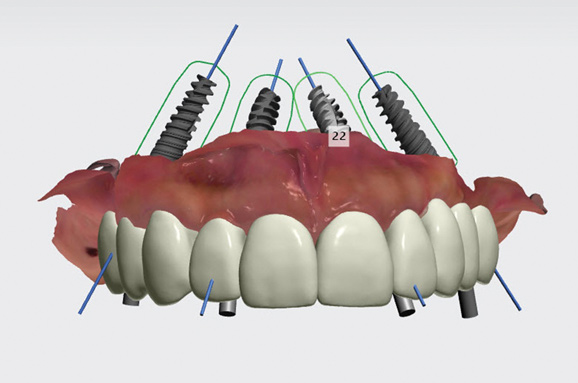

(19. AND 20.) Virtual implant planning of restorative treatment with facial analysis software.

Figure 19

Figure 20